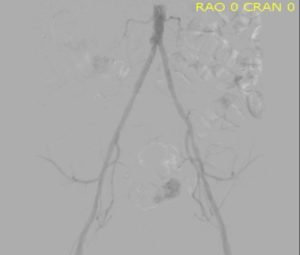

Hypoplastic small aorta

Angiography of a small aorta

The diagnosis of small aorta syndrome is often made with imaging studies such as a CTA. It is our personal experience that the imaging is not always ordered with this diagnosis in mind. Also, visceral abdominal ultrasound that is usually used for detecting abdominal aortic aneurysms can be used to measure the aorta. An aorta that is small can prompt further measurements of the iliac arteries and again the diagnosis can be made.

The largest series to date of small aorta syndrome described 30 women with narrowed aortas. Many of these women also had accelerated atherosclerosis. The presenting problem was intermittent claudication with reduced ankle brachial index. These women were treated successfully with percutanious transluminal angioplasty.